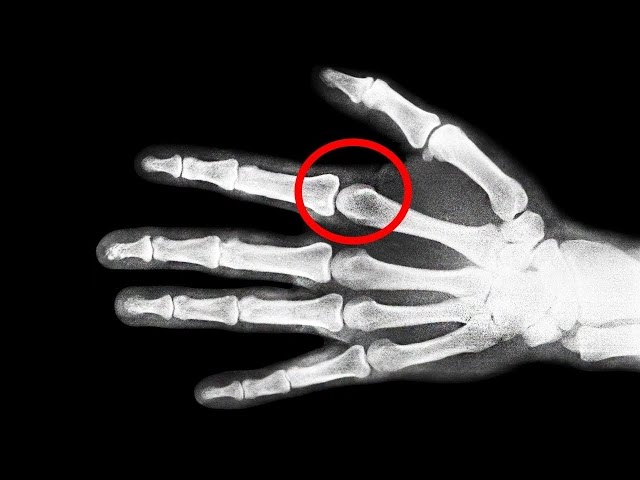

Probablemente eres parte del porcentaje de personas que a diario se crujen los dedos, y quizá, en mas de una ocasión te hayas preguntado si realmente hacerlo es malo o no para tus nudillos... En este video te hablaré de si es MALO crujirse los huesos de tus manos, y por ende, espero que tus dudas se resuelvan...

¿Es MALO Crujirse Los Dedos? ─ Mr. Tops